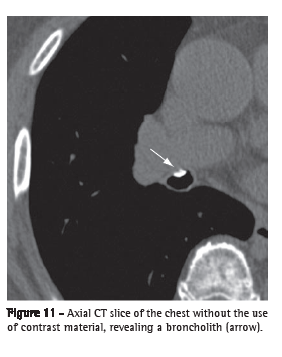

Broncholith (broncolito)

A broncholith is a calcified peribronchial lymph node that erodes into the adjacent bronchus. It is often secondary to infections by Histoplasma sp. or Mycobacterium ­tuberculosis. On CT scans, a broncholith is seen as a small focus of calcification within or adjacent to the airway, being more common in the middle lobe bronchus (Figure 11). Mucoid impaction, bronchiectasis or atelectasis might be observed distally.(24,25)